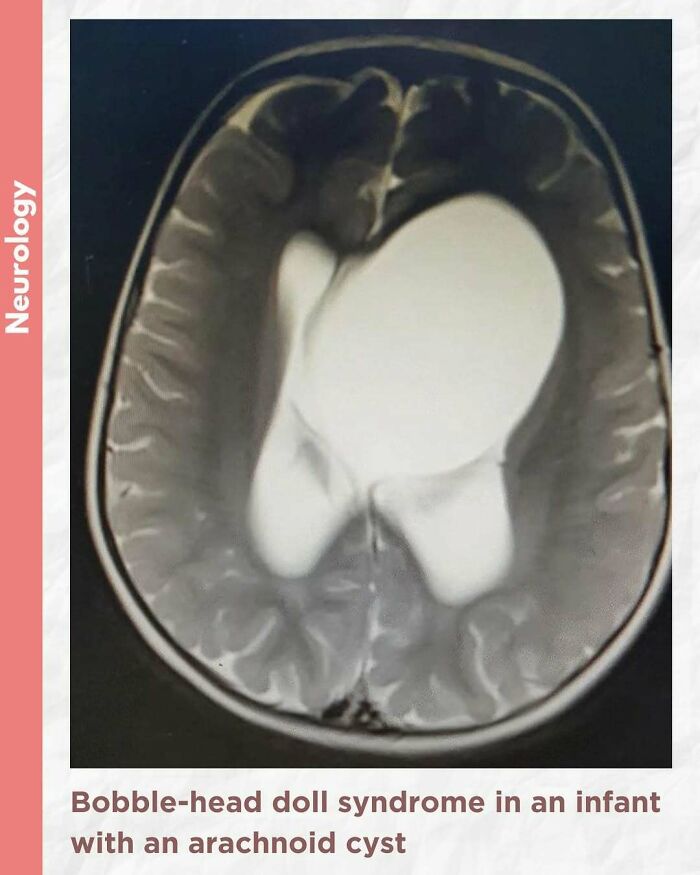

#54

Bobble-head doll syndrome in an infant with an arachnoid cyst

Bobble-head doll syndrome is a rare neurological movement disorder in which patients, usually children around age 3, begin to bob their head and shoulders forward and back, or sometimes side-to-side, involuntarily, in a manner reminiscent of a bobble head doll. The syndrome is related to cystic lesions and swelling of the third ventricle in the brain. Symptoms of bobble-head doll syndrome are diverse but can be grouped into two categories: physical and neurological. The most common form of treatment is surgical implanting of a shunt to relieve the swelling of the brain.

A 1.5-year-old girl presented to the pediatric clinic with the chief complaints of gradual onset excessive head nodding (side-to-side movement) for 3 months. Movements increased with walking, emotions, and stress; decreased during periods of concentration; and were absent during sleep. There were no other complaints or headaches. There was no other significant history.

The child was alert, with normal cognitive function. Neurological examination was normal. Initial laboratory assessment including CBC, hepatic and renal function, and endocrine function tests were normal.

Cranial MRI demonstrated a large left-hemispheric cystic process with a midline shift, well-defined thin-walled suprasellar arachnoid cyst measuring 3 × 5 × 7 cm that obstructed the foramina of Monro, with resulting hydrocephalus ventriculomegaly. Based on the cranial MRI and symptoms, a diagnosis of a suprasellar arachnoid cyst with BHDS was made. The patient underwent endoscopic cystoventriculostomy and cystocisternostomy for the suprasellar arachnoid cyst. During the 6 months of follow-up, the head bobbing disappeared completely, and her growth was normal.

Despite the rareness of bobble-head doll syndrome, it is considered an important condition that must be investigated early to detect the cause and treated promptly to avoid potential complications.